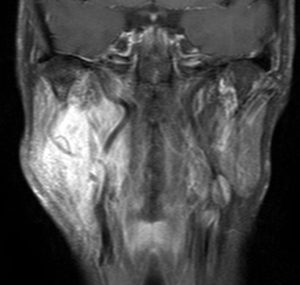

右はがドリニウム増強MRIです。NF-1患者さんの右深頸部のplexiform neurofibromaに発生したものです。通常の神経鞘腫に比較して境界が不鮮明で増大速度が早いことが特徴です。

- MRIでは境界不鮮明な不規則に増強される腫瘍です

- 大きなものでは全摘出することは不可能です

- 細い神経の分枝に沿って周囲に非常に広範囲に広がっています

- 周囲軟部組織,神経組織を巻き込んで浸潤していますので,剥離操作で摘出することができません